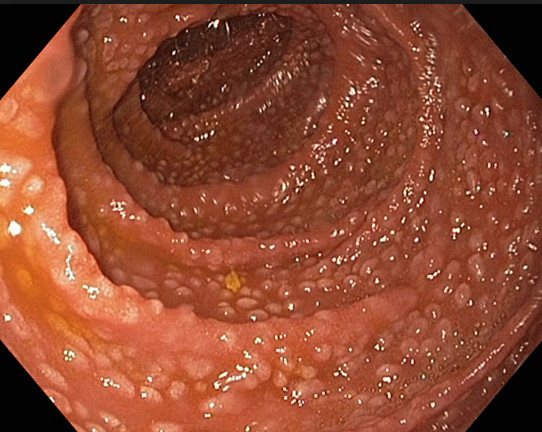

При эндоскопическом исследовании могут обнаружить совершенно случайно бессимптомно развивающуюся болезнь – фовеолярную гиперплазию желудка. Фовеолярная форма недуга – это бесконтрольное размножение клеток в слизистой оболочке или тканях пищеварительного органа. Она приводит к искривлению и утолщению складок слизистых оболочек желудка, удлиняет его отделы. Недуг не образует ни злокачественную, ни доброкачественную опухоль. Но является начальной стадией к развитию гиперпластических полипов.

Гиперплазия желудка нередко протекает бессимптомно, поэтому диагностика патологии на ранней стадии статистически происходит случайно, во время гастроскопии желудка в рамках подтверждения иной патологии.

Фиброгастродуоденоскопия (ФГДС) позволяет врачу визуально осмотреть стенки желудка и увидеть, чем является новообразование полипом или опухолью.

- Фиброгастродуоденоскопия. Одна из самых неприятных процедур для пациента. Но она дает точный результат, который помогает врачу увидеть картину болезни целиком. Такое обследование проводится путем введения внутрь органа аппарата. Благодаря ему специалист детально рассматривает имеющиеся полипы и прочие наросты.